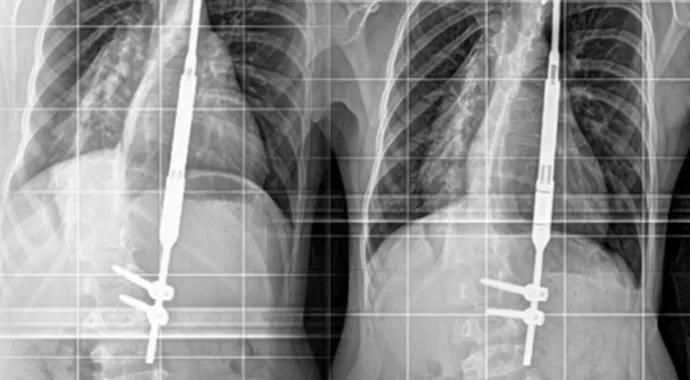

Posteroanterior radiographs of the boy with infantile idiopathic scoliosis who received the first MAGEC magnetic spinal growing rod at Cleveland Clinic. Top left: Image of the patient’s severe early-onset scoliosis at age 2 years, prior to surgical intervention. Bracing and casting had failed to control the deformity. Top right: Two years after placement of traditional growing rod instrumentation, prior to infection and the rod’s removal. Bottom left: Following placement of the magnetic growing rod in autumn 2014. Bottom right: After lengthening of the magnetic growing rod in the office. Note the expansion of the rod’s central barrel.